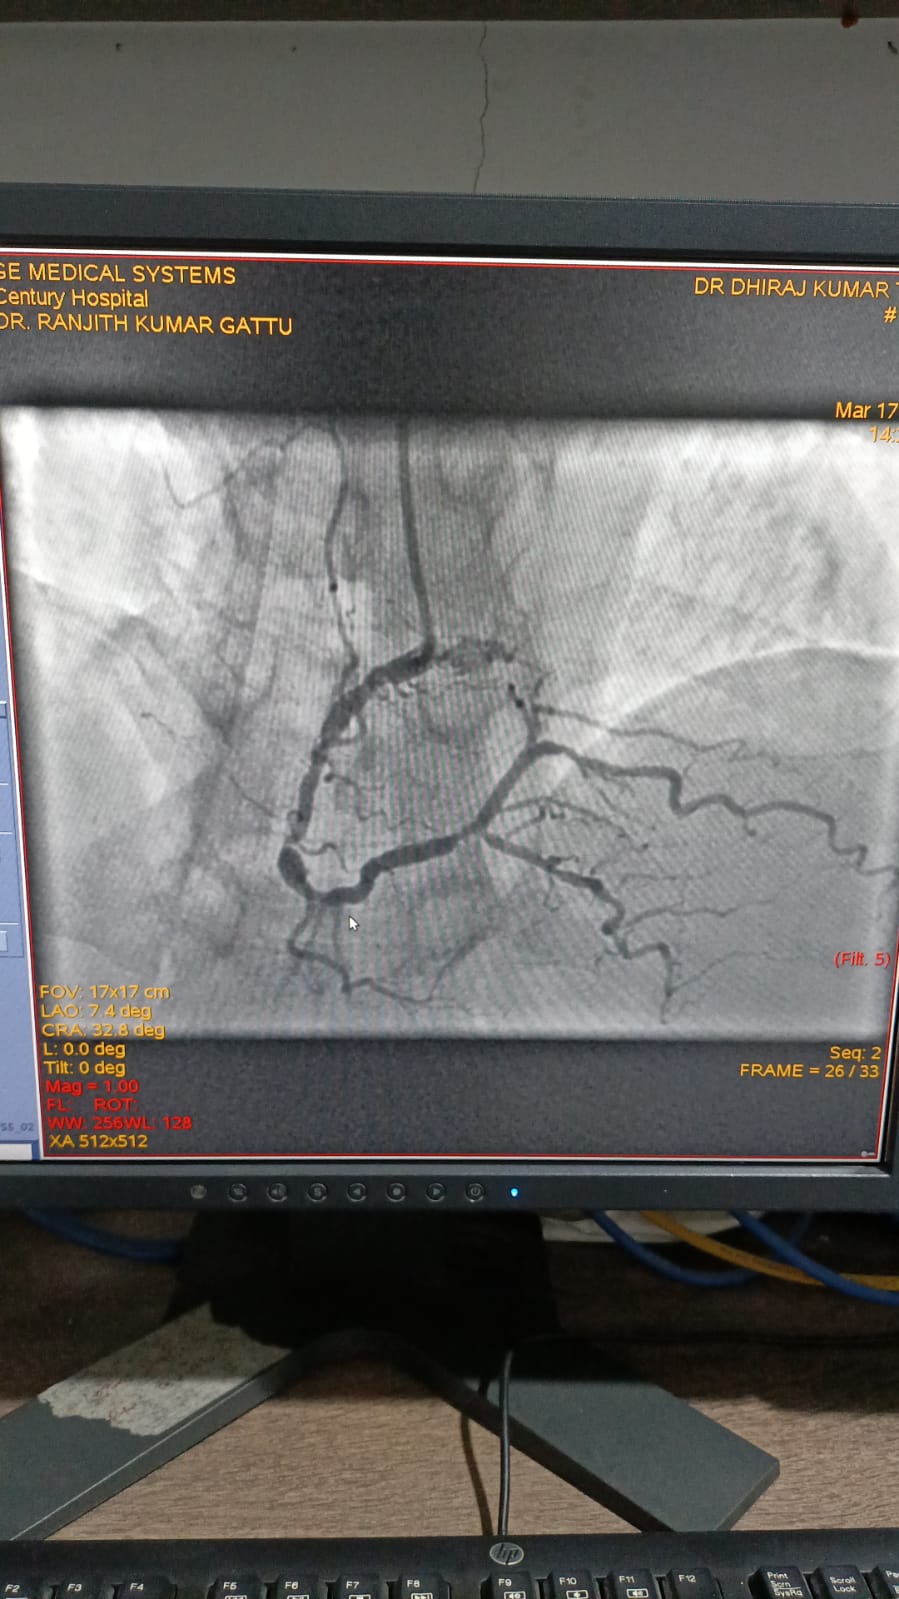

Left Coronary Diseased Artery